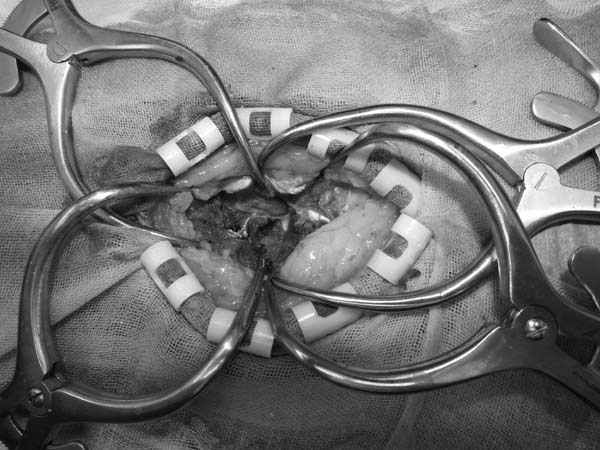

ワンちゃんが乳腺にできた複数のシコリを気にされて来院されました。bilateral mastectomyで対応しました。摘出後の病理組織検査の結果は、「R3-4間腫瘤:乳腺癌(複合型)」でそれ以外は「良性乳腺混合腫瘍」でした。無事元気に退院し、その後再発もなく経過は良好です。よかったね。